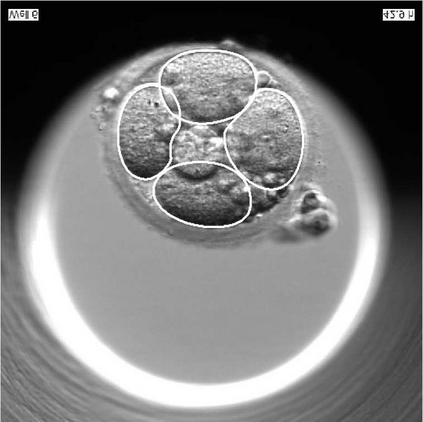

We present a novel method for identification of the boundary of embryonic cells (blastomeres) in Hoffman Modulation Contrast (HMC) microscopic images that are taken between day one to day three. Identification of boundaries of blastomeres is a challenging task, especially in the cases containing four or more cells. This is because these cells are bundled up tightly inside an embryo's membrane and any 2D image projection of such 3D embryo includes cell overlaps, occlusions, and projection ambiguities. Moreover, human embryos include fragmentation, which does not conform to any specific patterns or shape. Here we developed a model-based iterative approach, in which blastomeres are modeled as ellipses that conform to the local image features, such as edges and normals. In an iterative process, each image feature contributes only to one candidate and is removed upon being associated to a model candidate. We have tested the proposed algorithm on an image dataset comprising of 468 human embryos obtained from different sources. An overall Precision, Sensitivity and Overall Quality (OQ) of 92%, 88% and 83% are achieved.